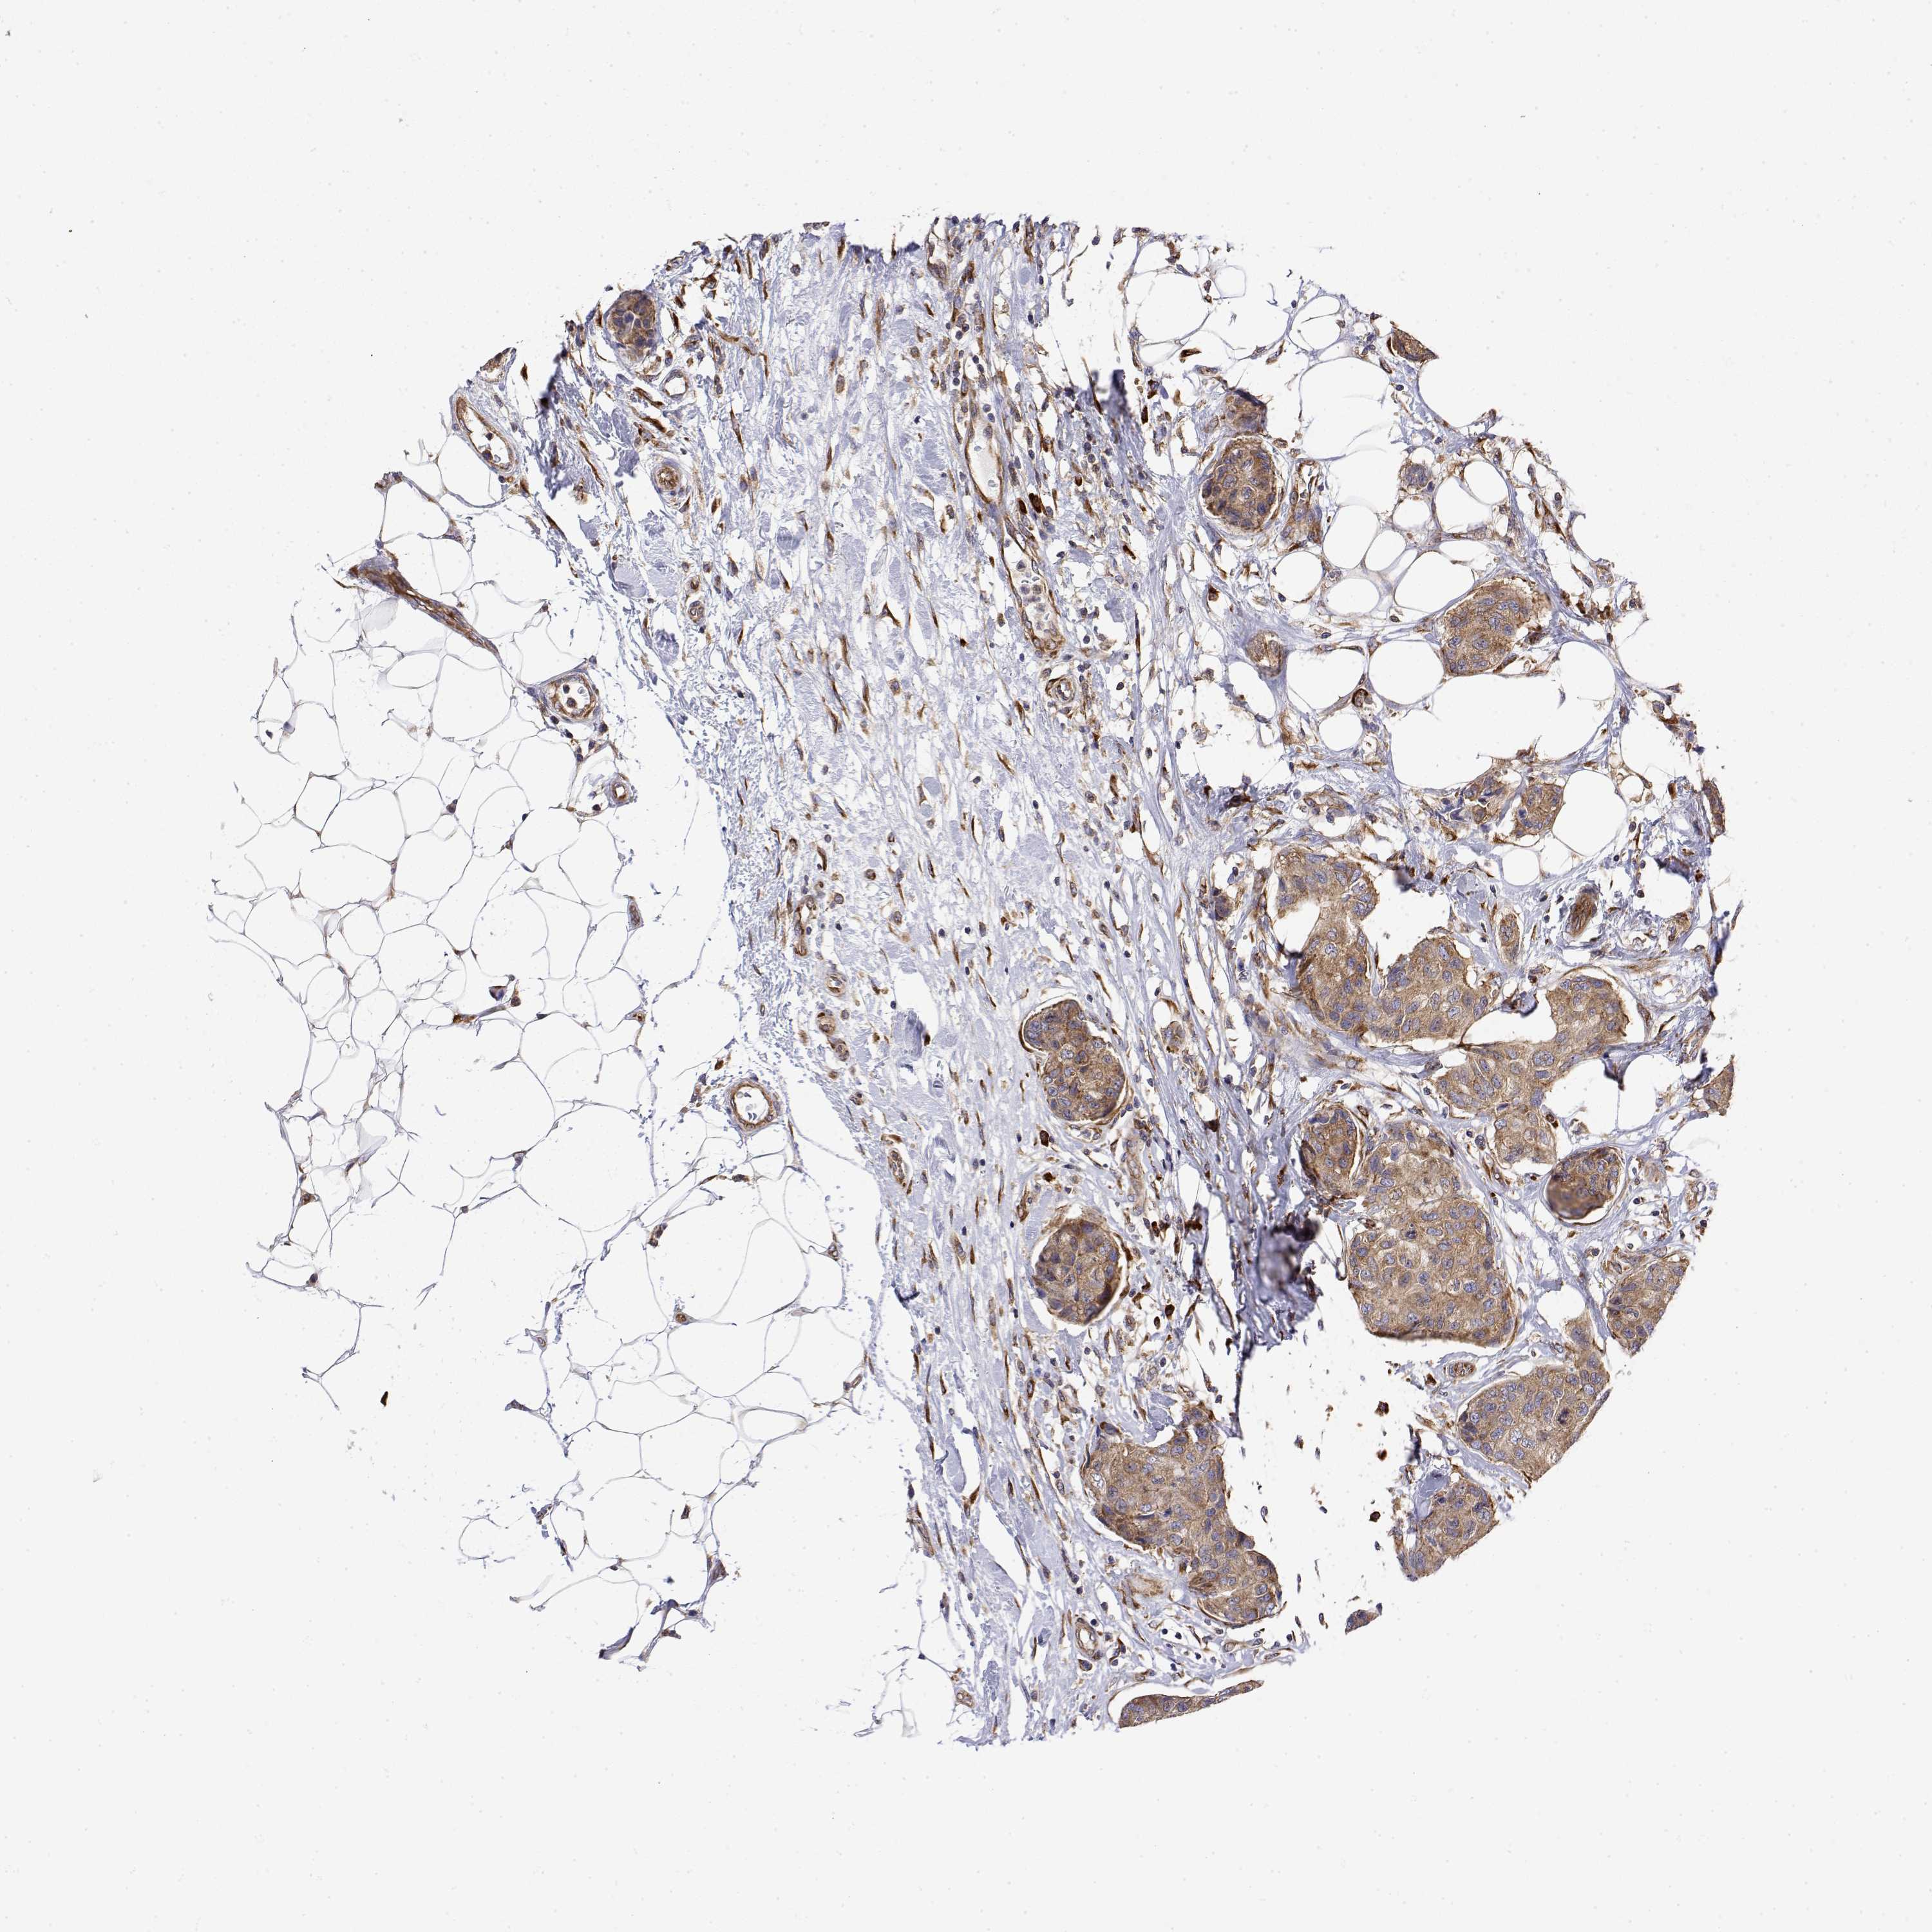

CANCER BREAST CANCER Show tissue menu

BRCA TCGA BRCA VALIDATION PROTEIN EXPRESSION